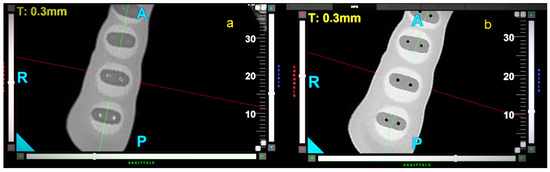

Effects of Three Types of Movements of Nickel–Titanium Instruments on Root Canal Preparation: Analysis by Using Cone-Beam Computed Tomography

by Kinga Kaczor-Wiankowska, Maciej Czechowski, Philipp Arndt, Aleksandra Joanna Wiankowska, Weronika Kwiecień and Katarzyna Lewusz-Butkiewicz

Materials 2025, 18(23), 5417; https://doi.org/10.3390/ma18235417 - 1 Dec 2025

The development of endodontics leads to increasingly innovative techniques, which improve mechanical root canal preparation. Endostar E3 Azure (Poldent Co., Warsaw, Poland) is a nickel–titanium file, which can be used in rotary, reciprocal, and optimum torque reverse (OTR) movements. The aim of this [...] Read more.

The development of endodontics leads to increasingly innovative techniques, which improve mechanical root canal preparation. Endostar E3 Azure (Poldent Co., Warsaw, Poland) is a nickel–titanium file, which can be used in rotary, reciprocal, and optimum torque reverse (OTR) movements. The aim of this study was to assess canal transportation (CT), canal-centering ability (CCA), and wall thickness reduction (WTR) after the use of Endostar E3 Azure files in these three movements. In total, 24 two-canal artificial teeth were used, which were divided into three groups, depending on the applied movement (n = 16 canals). Each canal was initially prepared manually and then instrumented with Endostar E3 Azure files using rotary, reciprocal, or OTR movements. Cone-beam computed tomography was performed before and after canal preparation. The root wall thickness was measured at 3 mm, 6 mm, and 9 mm from the radiological apex and CT, CCA, and WTR were calculated. Reciprocal movement resulted in significantly better outcomes in canal-centering ability (CCA = 0.57) compared with rotary movement (CCA = 0.27) in the middle part of the canal. The wall thickness was significantly reduced in the rotary group: 0.21, 0.19, and 0.13; in the reciprocal group: 0.09, 0.08, and 0.1; and in the OTR group: 0.11, 0.15, and 0.17 at 3, 6, and 9 mm from the apex, respectively. Moreover, rotary movement caused a statistically greater reduction in wall thickness in the apical and middle area compared to other groups. Endostar E3 Azure files significantly reduce the thickness of the root wall along its entire length, which may indicate the effective removal of infected tissue. The use of OTR movement did not affect the analyzed parameters negatively, and it is a safe option which combines the advantageous features of rotary and reciprocal movements. Full article